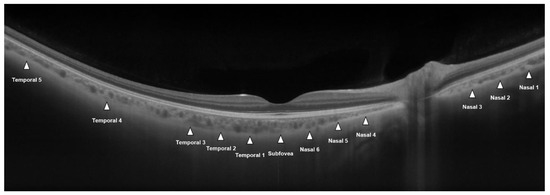

2.2. Image Acquisition

2.3. CT Measurements